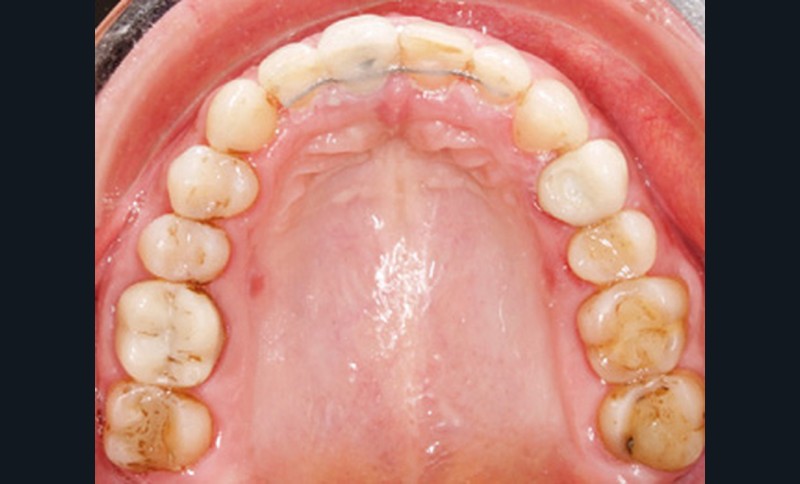

Examen endobuccal (fig. 2a-e)

L’arcade maxillaire est asymétrique et parabolique. Elle présente une mésio-position du secteur 1. On note des rotations mésio-vestibulaire de 13 et disto-vestibulaire de 23 et une palato-version incisive. Les restaurations prothétiques sur 11, 16 et 24 semblent à refaire. L’arcade mandibulaire est asymétrique et parabolique avec une couronne sur implant en 36.

Dans la dimension transversale, on constate une endoalvéolie maxillaire. Dans la dimension sagittale, on observe une classe II plus importante à droite où elle est complète de 5 mm. Le surplomb est absent et la supraclusion totale (6 mm) par supra-alvéolie mandibulaire.